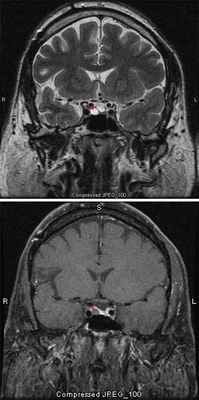

МРТ является основным методом диагностики, с помощью которого выявляются аденомы гипофиза разных размеров. Компьютерную томографию применяют реже и в основном в тех случаях, когда необходимо провести визуализацию твердых тканей, стенок турецкого седла и образований, которые распространились за его пределы.

Динамическая магнитно-резонансная томография с контрастным усилением считается наиболее информативным методом для оценки небольших образований в области гипофиза. С помощь томографа можно определить границы и размеры опухоли, при этом обеспечивается высокая четкость разрешения на снимке.

Клинические признаки хромофобной аденомы

Хромофобная аденома проявляется в височных болях, ухудшении зрения, импотенции, бесплодии. В начале заболевания отмечается ожирение. Кожные покровы сухие, бледные. У мужчин может проявляться в старческом виде. Развивается кахексия, выпадение волос на всем теле, брадикардия, пониженное АД. При надавливании на соски может появляться молокообразная жидкость.

На фото аденома гипофиза выглядит как узел круглой либо овальной формы.